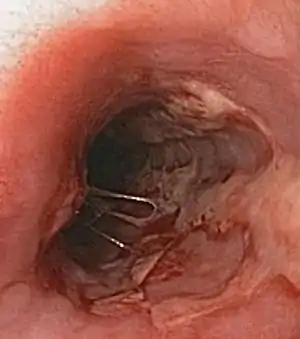

Herpes esophagitis Symptoms may include painful swallowing (odynophagia) and difficulty swallowing (dysphagia). It is often associated with impaired immune function (e.g. HIV/AIDS, immunosuppression in solid organ transplants).